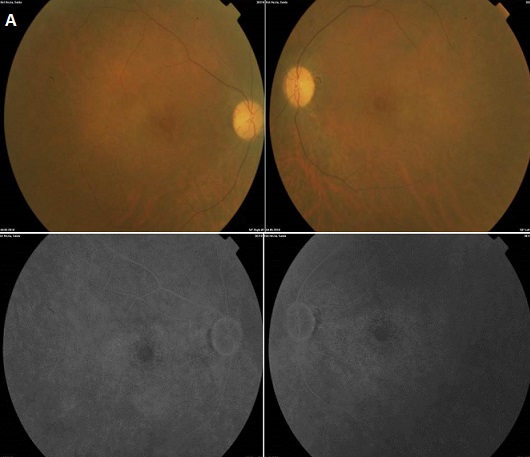

Il s'agit du cas d'une patiente âgée de 52 ans, aux antécédents de lupus érythémateux systémique(LES) évoluant depuis 1997, actuellement sous Nivaquine (APS) à la dose de 2 comprimés par jour, adressé pour baisse de la vision bilatérale. L'examen de l'oeil droit trouve une vision corrigée à 1/10, un segment antérieur d'aspect normal et au fond d'oeil une maculopathie en cocarde (A). L'examen de l'oeil gauche trouve une vision corrigée à 2/10 faible, un segment antérieur calme et au fond une maculopathie en cocarde. L'angiographie rétinienne à la fluorescéine montre une image en oeil-de-boeuf bilatéral (B).